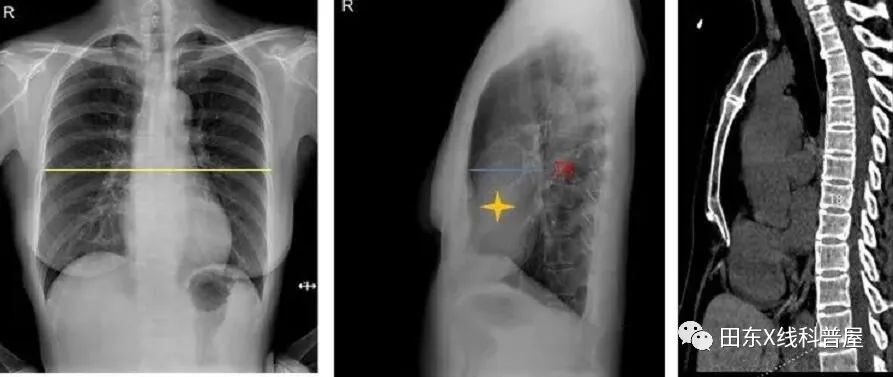

患者男,17岁,胸痛6年,偶有胸闷,活动后明显,休息后可缓解

曾于当地医院就诊,听诊心脏有轻微杂音(具体不详),行心脏超声检查无异常

胸椎曲度弧高(左侧位胸片测量):T4-T12做一连线,测T8椎体前缘与该直线的垂直距离,其距离若<12mm,可考虑SBS。

测量胸廓前后径/横径比值≤0.33。